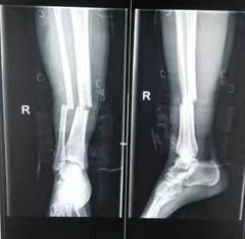

最近65岁的刘阿姨(化名)下楼梯时不慎摔伤了右腿,小腿肿胀并疼痛得厉害,到我院创伤外科就诊,医生看了片子说这是右胫腓骨骨折。图片图片